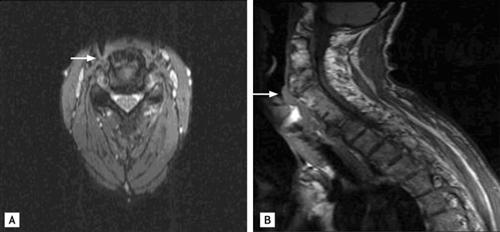

相关图片